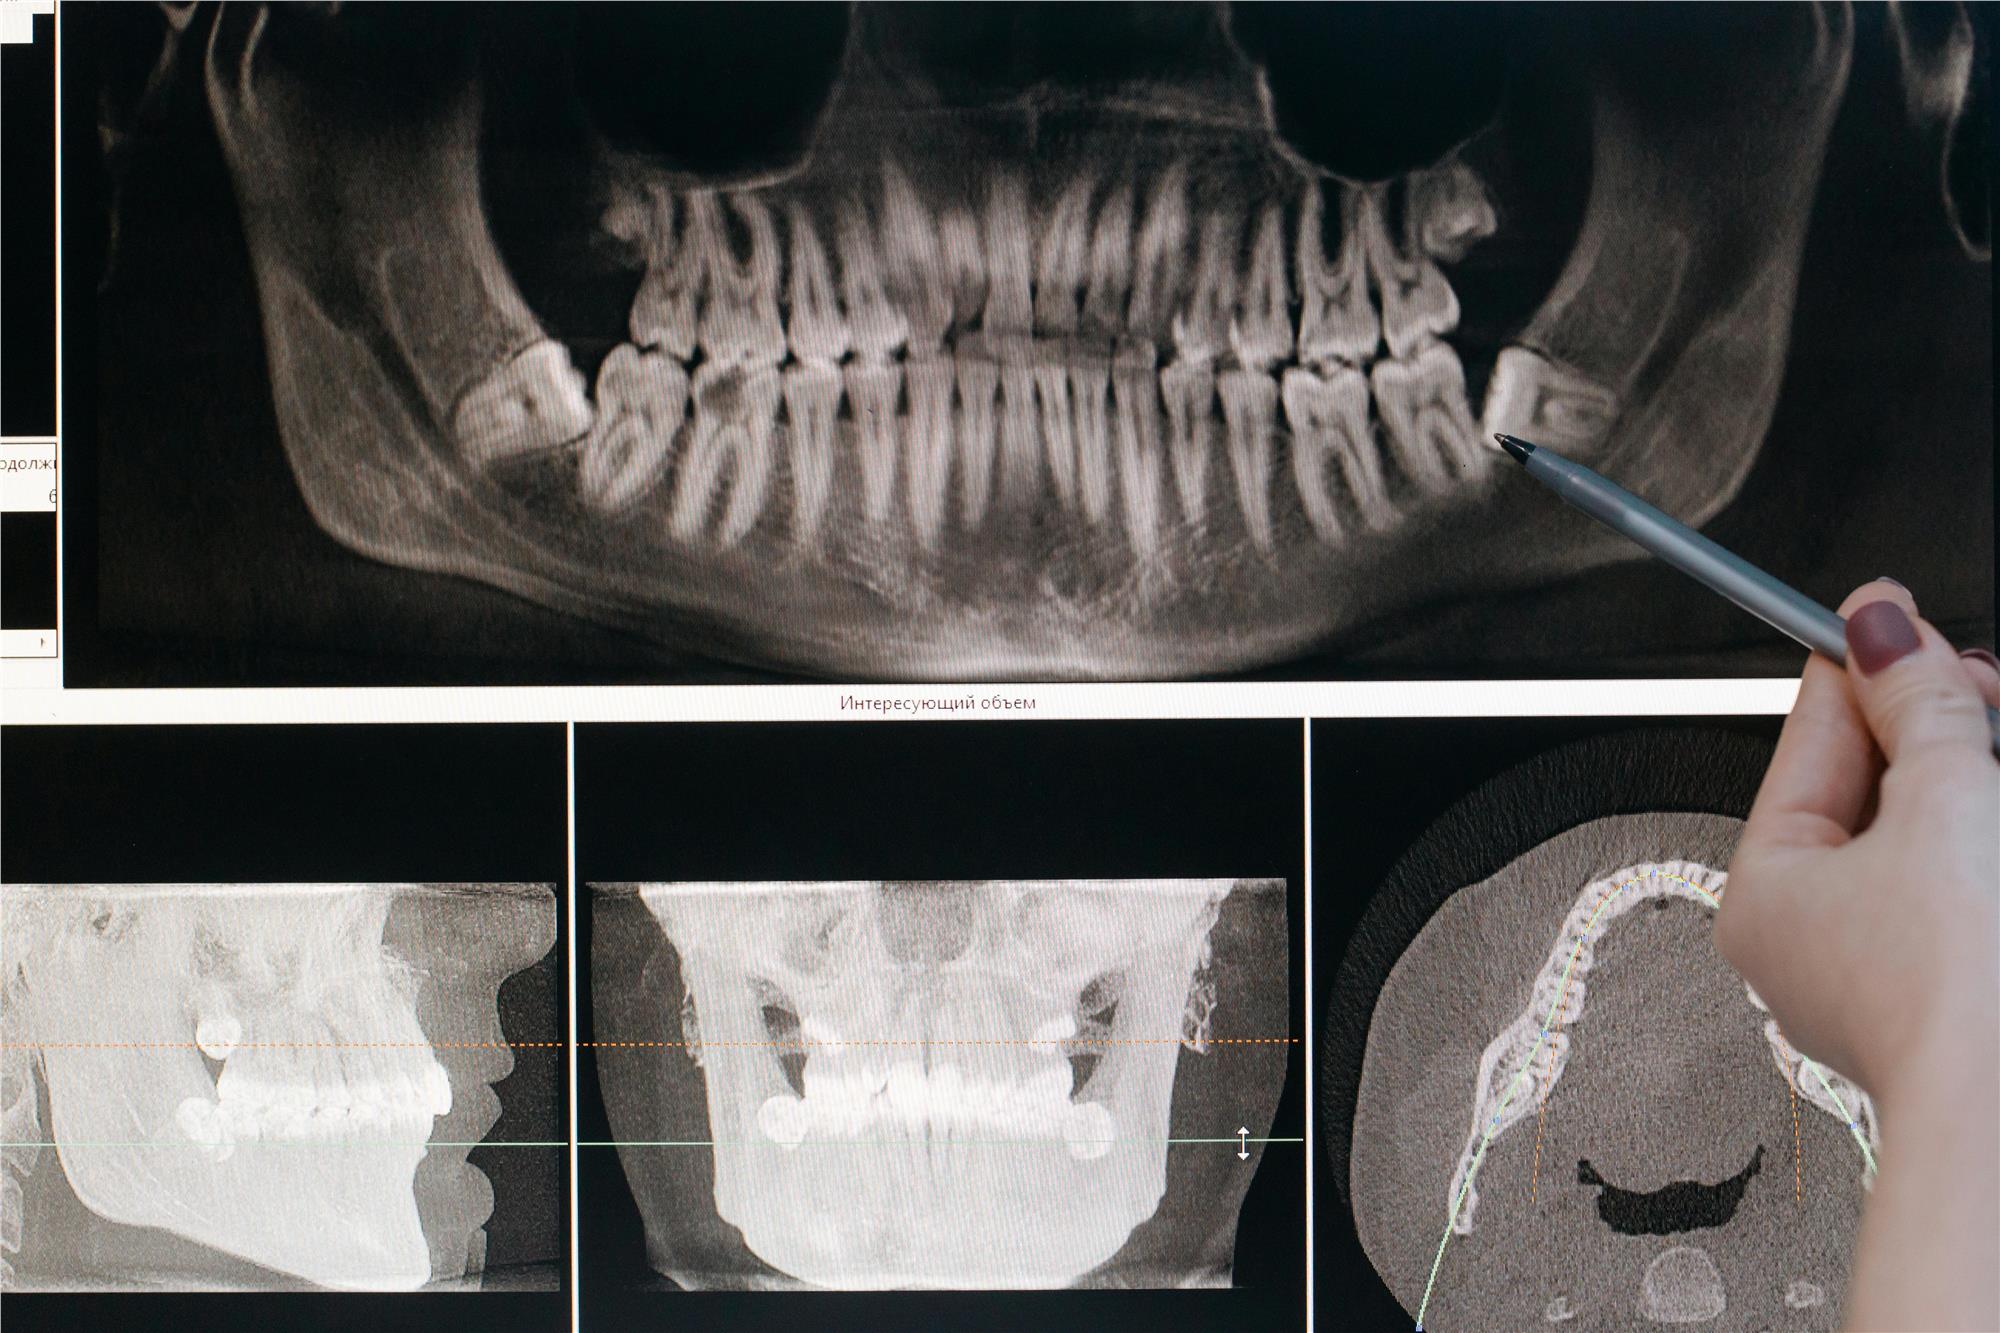

Zahn-Röntgenaufnahmen

Zahn-Röntgenaufnahmen können Ihrem Zahnarzt helfen, Probleme mit der Mundgesundheit, insbesondere Karies und Zahnfleischerkrankungen, zu erkennen, bevor sie sich verschlimmern. Es gibt viele verschiedene Arten von Zahn-Röntgenaufnahmen, sowohl intraoral als auch extraoral. Zahn-Röntgenaufnahmen sind ein wichtiges Instrument für angemessene Mundgesundheit und -pflege.